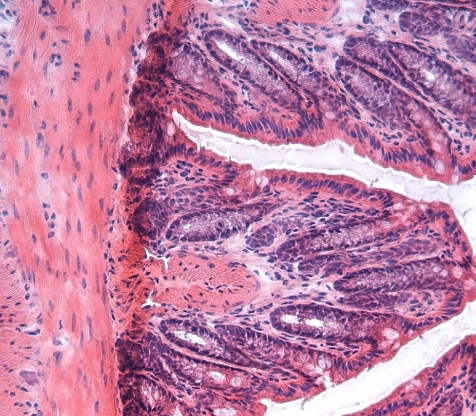

Dextran sulfate sodium for colitis (DSS)

Dextran sulfate sodium (DSS) is the goldened standard for inducing colitis in experimental animals. DSS is a dextran sulfate with a mean molecular with of 40 kDa and a sulfur content of 17-19 %. About 40 years ago, TdB Labs was involved in the work which led to the development of colitis grade DSS.

TdB Labs’ non-fluorescent derivatives include e.g. dextran sulfates and charged polysaccharides like CM- and DEAE-dextran. One of our most popular predicts is dextran sulfate sodium (DSS), which has been used to induce colitis in mice and rats for more than 20 years. Dextran sulfates of lower molecular weights are often used as a cell media additive or as stabilisers.